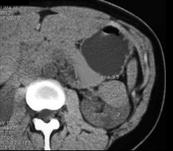

问题 女,35岁,请根据所示图像,选择最可能诊断 ( )

选项 A、左侧肾盂旁囊肿 B、左侧囊性肾癌 C、左侧高密度肾囊肿 D、左侧肾积水 E、左侧单纯性肾囊肿

答案 C